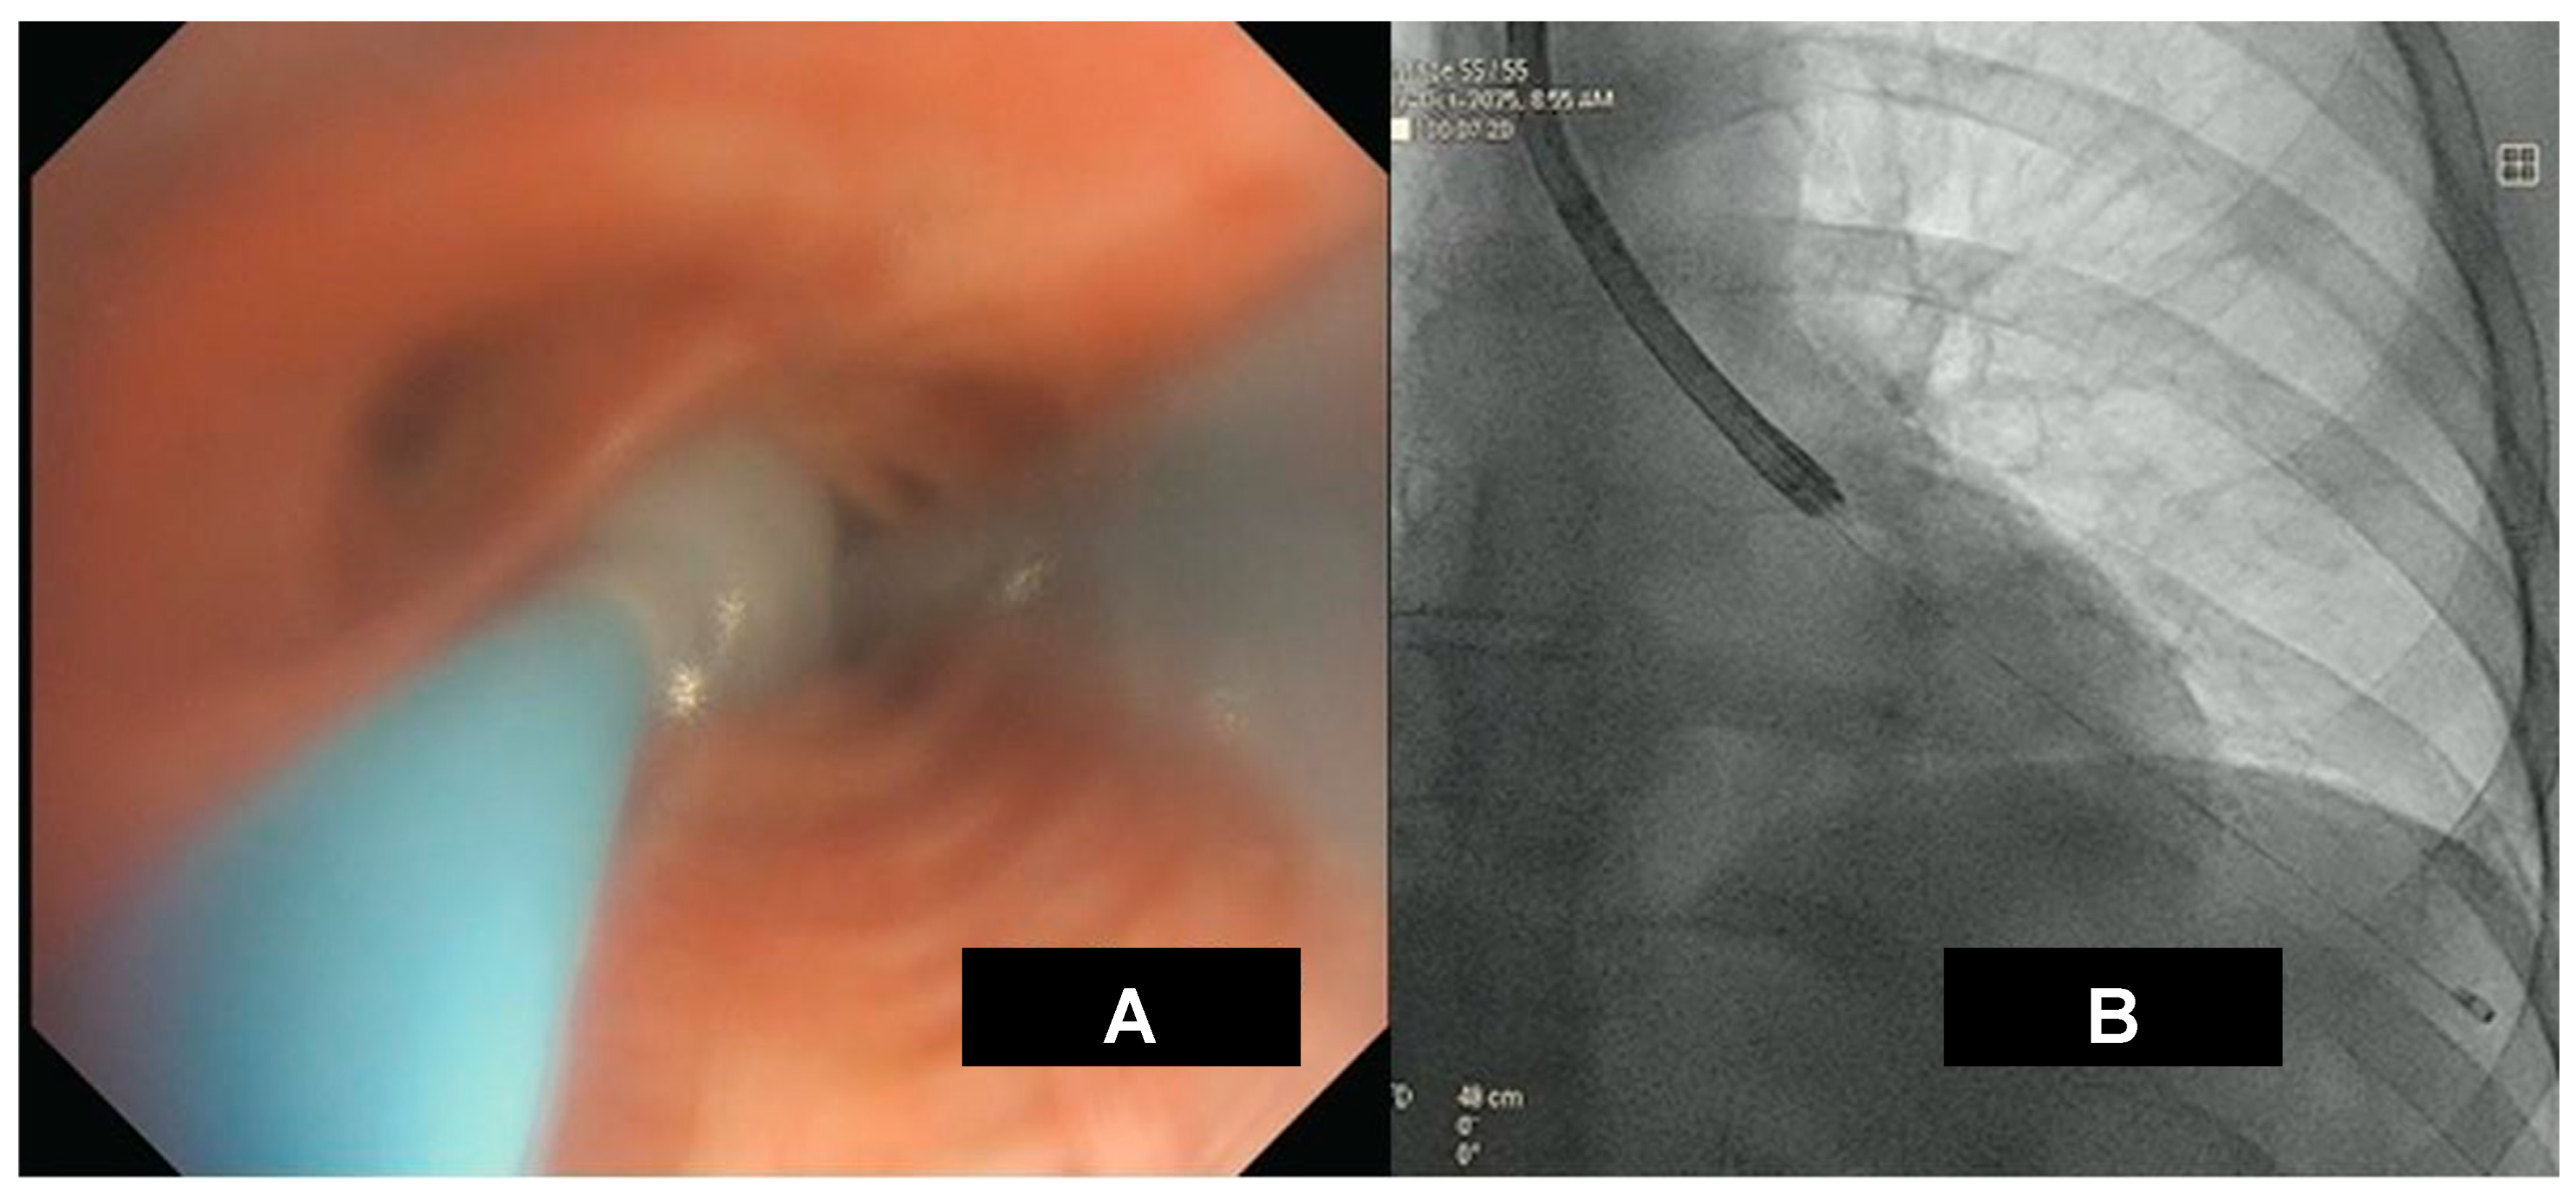

HRCT is the preferred imaging modality for the diagnosis, management, and monitoring of post-COVID-19 ILD. HRCT scans identify the location and distribution of lung abnormalities, which can be bilateral, peripheral, or mid- to lower-lobe parenchymal changes. The most common HRCT patterns are ground-glass opacities, indicative of alveolar spaces filled with cells or fluid, alveolar wall thickness, and a reticular pattern, typical of ILD [20]. The extent of HRCT abnormalities correlates closely with symptom severity and TLC reduction, in agreement with National Institute of Health findings [18]. HRCT allows: (1) early fibrosis detection; (2) treatment guidance, including use of antifibrotic drugs; and (3) prognostic assessment via serial imaging or scale evaluation [23].

A potential radiologic sign of HRCT is the atoll sign, or the reversed halo sign. The characteristic image shows a central area of ground-glass opacity surrounded by a ring of denser consolidation. This pattern can be suggestive of organizing pneumonia (OP) and is found in a variety of pulmonary diseases like fungal infections in neutropenic patients, granulomatosis with polyangiitis, and various tumors such as lung adenocarcinoma and lymphoma. Histopathology shows that the central ground-glass opacity corresponds to septal inflammation, while the peripheral ring relates to inflammation of the alveolar ducts or airspaces.

Further, the crazy paving pattern, characterized by ground-glass opacities with interlobular and intralobular septal thickening, has been observed in HRCT imaging associated with COVID-19. HRCT patterns are non-specific because they can be found in alveolar proteinosis, ARDS, and other interstitial pneumonias [24,25]. Studies have identified different HRCT patterns between early and more advanced disease stages. The latter showed an increase in pleural changes including subpleural lines and effusions. HRCT patterns are shown in Figure 3.

Figure 3. Radiological imaging in COVID-19 infection. HRCT patterns in Acute Respiratory Distress Syndrome (ARDS) (A) and in subacute phase with atoll or reversed halo sign ((B) arrow).